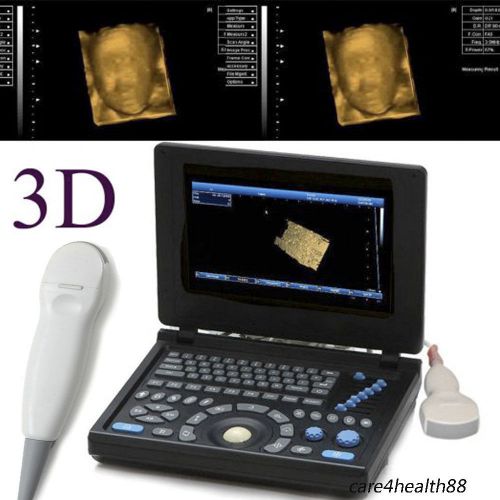

Model | RUS-9000E2 |

3D PC Full-digital Ultrasound scanner machine 3.5MHz Convex + Linear+ Tvaginal

3D PC Full-digital Ultrasound scanner machine 3.5MHz Convex +mirco-Convex probe

3D Full Digital Laptop Ultrasound Scanner (PC) With Convex probe & Transvaginal